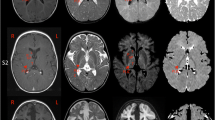

Two patients previously published representing the spectrum of mild and severe ABAT deficiency patients were studied for metabolomics profile. Subject 1 presented in infancy with a severe encephalopathy including intractable seizures, hypotonia, and lethargy (Besse et al. 2015). Brain MRI showed extensive symmetric signal abnormalities in several regions including posterior limbs of the internal capsule, cerebral peduncles, dorsal tegmentum and pons, medulla, and dentate nuclei indicating significant hypomyelination and brain atrophy. This child never achieved any developmental milestones and remains alive in a static state at age 9. This child is one of three similarly affected siblings all of whom were demonstrated to be homozygous for ABAT NM_000663.4 c.631C>T; NP_000654.2 p.Leu211Phe (Besse et al. 2015, 2016).

Subject 2 presented to clinic at 6 months with global developmental delay, hypersomnolence, hypotonia, bilateral opthalmoplegia, and mild choreiform movements without apparent epilepsy (Besse et al. 2016). Oculomotor apraxia was appreciated by age 18 months and cranial MRI conducted showed extensive signal abnormalities in the deep white matter indicative of diffuse, mild hypomyelination. In contrast to Subject 1, no brain atrophy was apparent on MRI. Genetics studies showed this child was compound heterozygous for ABAT NM_000663.4 c.454C>T;p.Pro152Ser and c.1393G>C;p.Gly465Arg.

For both subjects prior to molecular genetic studies, CSF was tested for a panel of neurotransmitters that was reported normal; however, GABA was not included in this panel testing. After molecular studies pointed to ABAT as the pathogenic gene, Subject 1 was tested by proton NMR spectroscopy which showed elevated GABA in the brain (Besse et al. 2015). Subject 2 exome studies identified compound heterozygous mutations in ABAT that were reported as variants of uncertain significance (VUS). Subsequent studies of cerebral spinal fluid (CSF) in this patient demonstrated free GABA level of 247 nmol/L (17–67) and total GABA level of 33.4 μmol/L (4.2–13.4).

Metabolomics screening showed abnormalities in both patients. Subject 1 had metabolomics screening conducted on plasma when he was 5 years and was not receiving flumazenil treatment. This testing showed 2-pyrrolidinone elevated more than 2 standard deviations (SD) above normal (z-score = 3.7) (Fig. 1b). Similarly, at age 1 year, Subject 2 had metabolomics screening in plasma, urine, and CSF all of which showed 2-pyrrolidinone elevated above normal (z-score = 6.1, 4.24, and 7.1) (Fig. 1b). Glutamate, which is just prior to GABA in the GABA shunt, was normal in all samples, as was alpha-ketoglutarate, which is just prior to glutamate and the metabolite that flows from the citric acid cycle to the GABA shunt (Fig. 1). Succinic semialdehyde, which is the product of GABA-T catabolism of GABA in the GABA shunt, was not measured. However, metabolites of the Kreb’s cycle that are just post GABA shunt were in the normal range: succinate, fumarate, and malate.